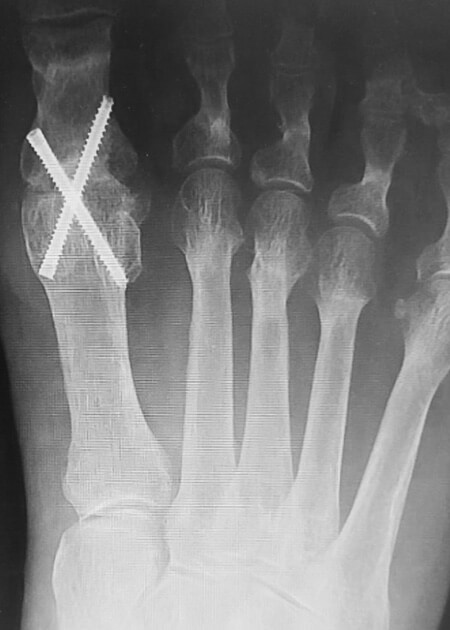

Antes y después

Te mostramos algunos ejemplos de antes y después de resolución de hallux rigidus con cirugía mínimamente invasiva del pie.